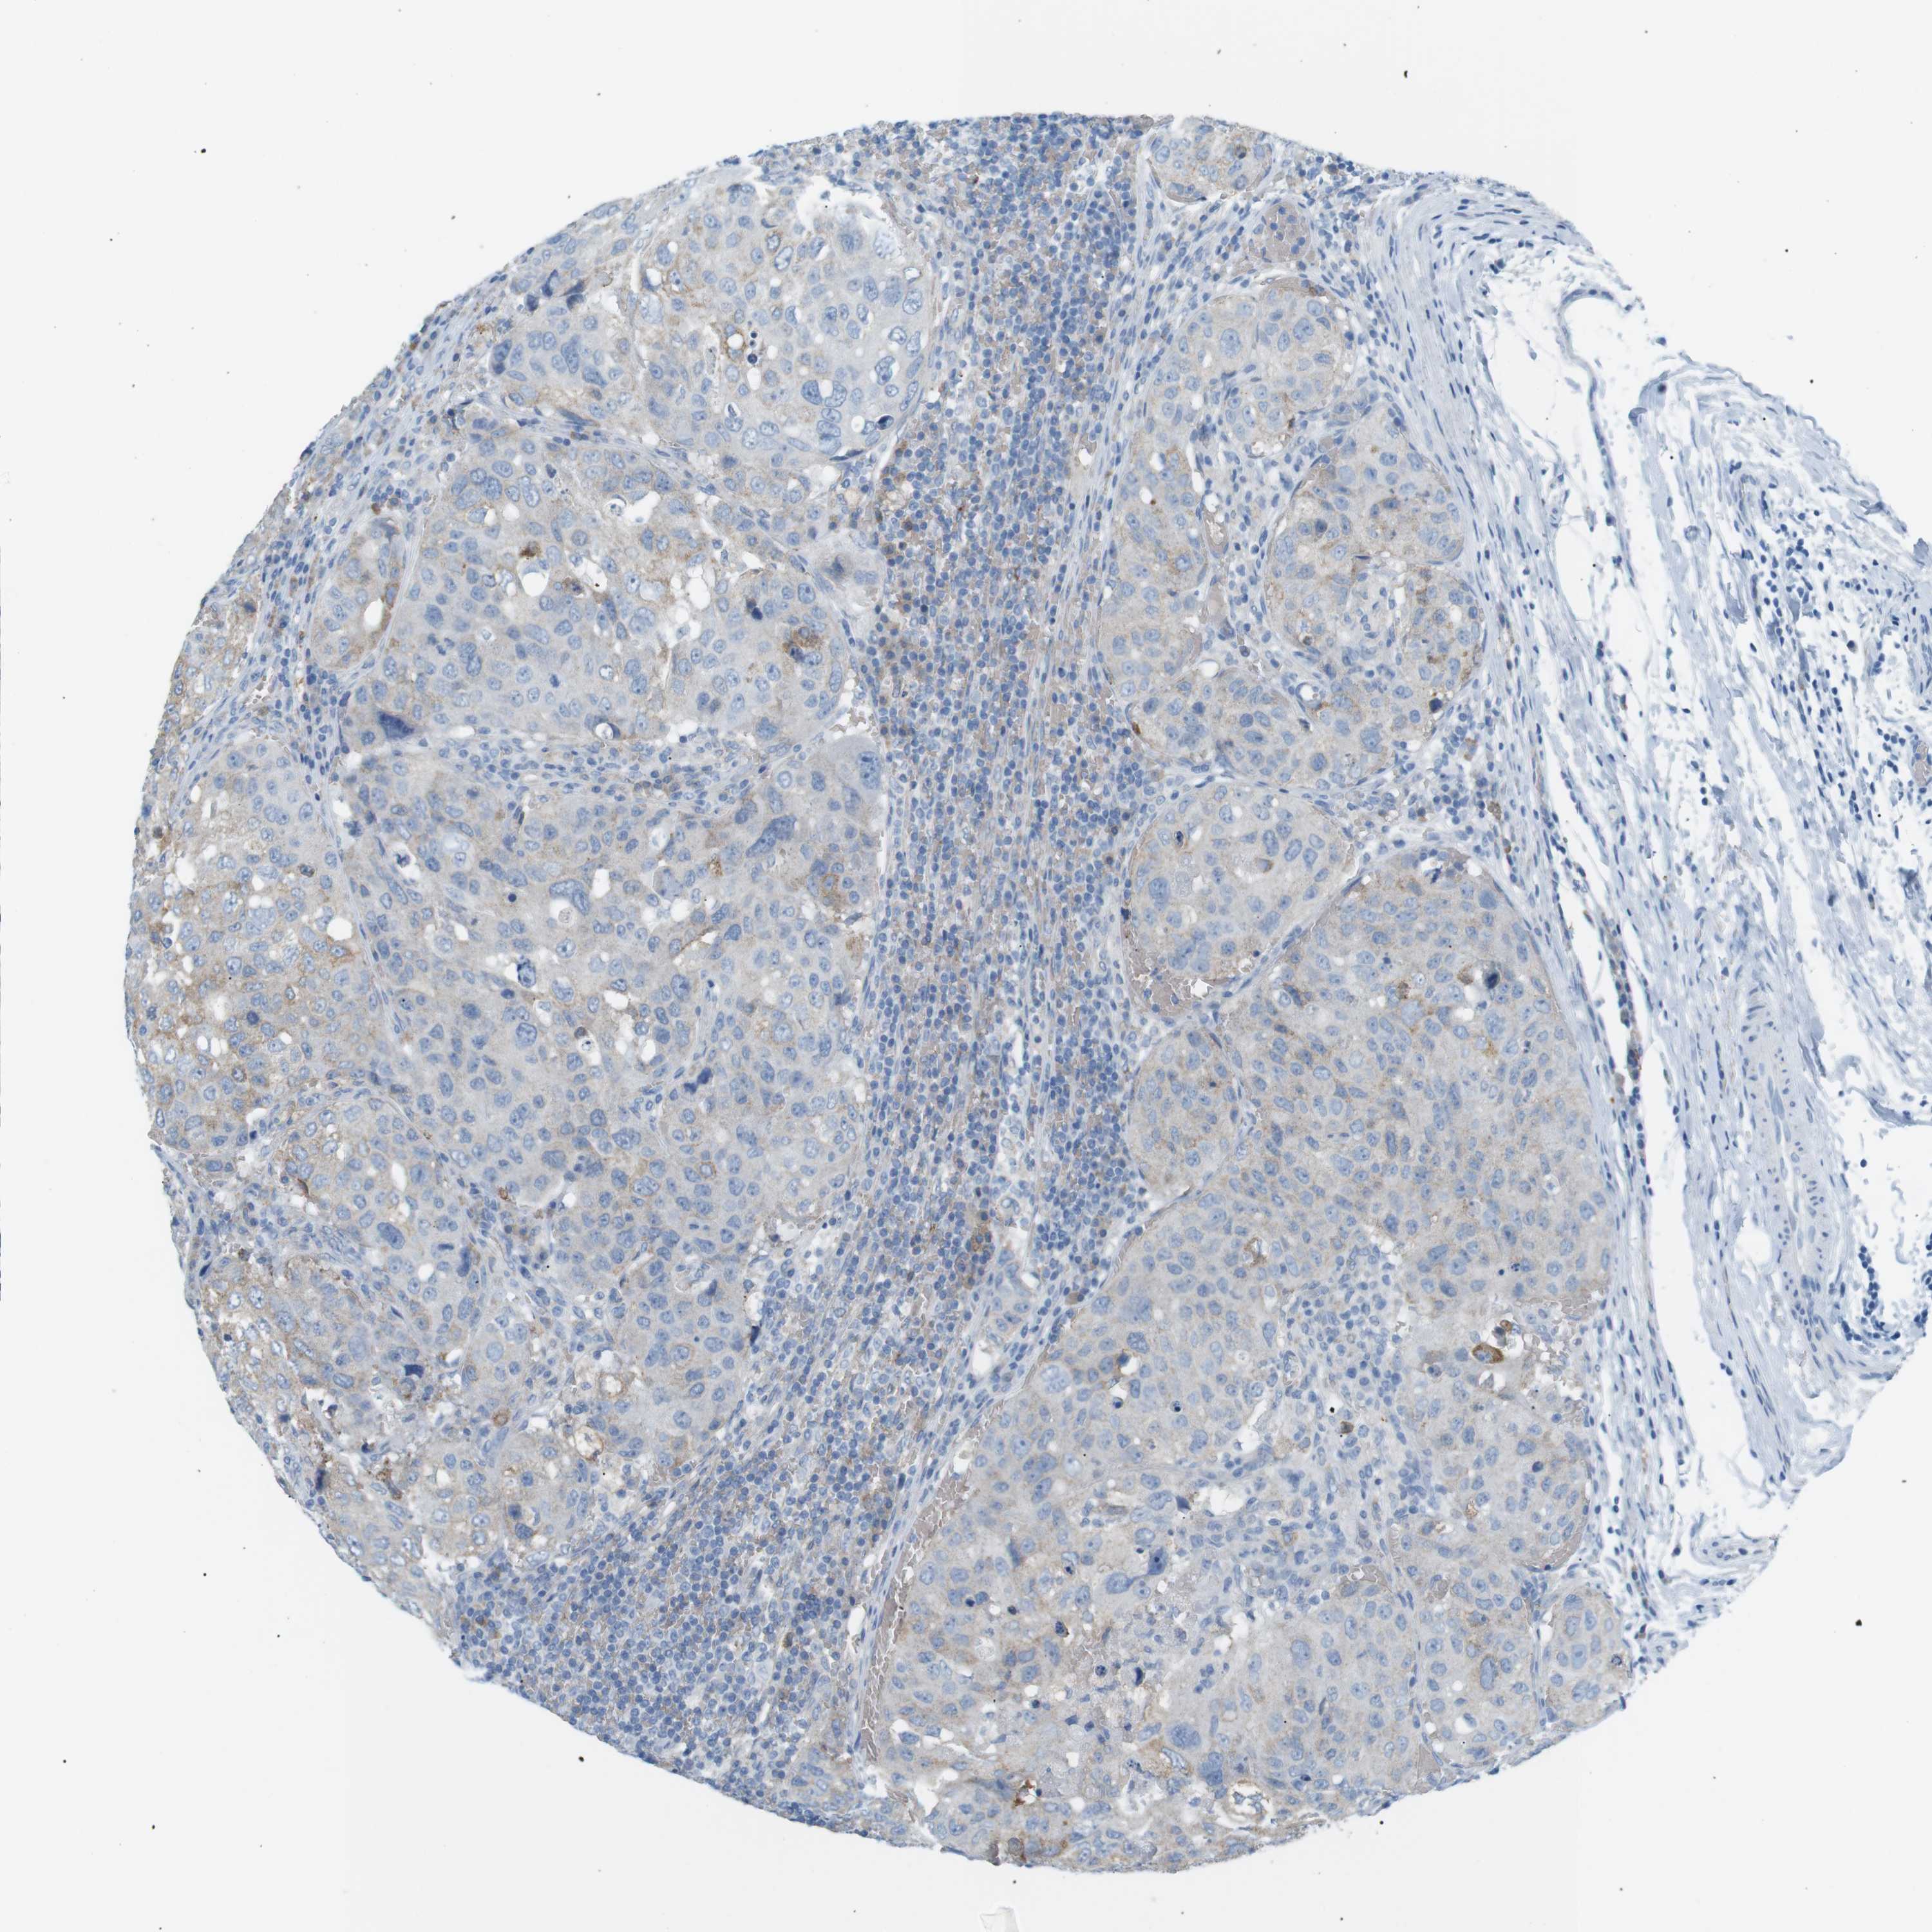

UROTHELIAL CANCER - Protein expressioni

A mouse-over function shows sample information and annotation data. Click on an image to view it in a full screen mode. Samples can be filtered based on level of antibody staining by selecting one or several of the following categories: high, medium, low and not detected. The assay and annotation is described here.

Antibody stainingi

Antibody staining in the annotated cell types in the current human tissue is reported as not detected, low, medium, or high, based on conventional immunohistochemistry profiling in selected tissues. This score is based on the combination of the staining intensity and fraction of stained cells.

Each image is clickable and will lead to virtual microscopy that enables deeper exploration of all samples and also displays staining intensity scores, fraction scores and subcellular localization as well as patient and tissue information for each sample.

Antibody CAB016119

Urothelial carcinoma, High grade

Urothelial carcinoma, Low grade

Adenocarcinoma, NOS